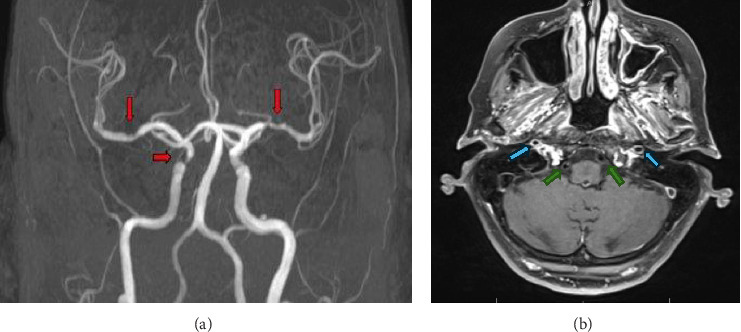

Giant cell arteritis (GCA) is an inflammatory vasculitis affecting large and medium-sized arteries, leading to complications such as arterial dissection, blindness, and stroke. Rarely, GCA presents with Horner's syndrome due to sympathetic neuron involvement from arterial inflammation. This case report discusses an 82-year-old female with hypertension, atrial fibrillation, and arthritis who presented with a 24 h history of right eye ptosis, blurred vision, dizziness, and aching eye pain. She had a mild headache and tenderness over the right temporomandibular joint but no temporal artery tenderness. Examination revealed right eye ptosis and miosis, indicative of Horner's syndrome, with no other neurological deficits. Lab results showed elevated ESR (68 mm/h) and CRP (16 mg/L). MRI with contrast revealed mild to moderate stenosis and enhancement in bilateral MCAs and basilar artery with inflammation in the right distal extracranial ICA, suggesting an inflammatory process. The patient was started on prednisone 40 mg daily. A temporal artery biopsy confirmed GCA with characteristic histopathological findings. Her prednisone dosage was increased to 60 mg/day, and she was started on tocilizumab. This case underscores the need to consider GCA in patients with Horner's syndrome and the importance of vessel wall imaging, as early corticosteroid treatment can prevent complications like vision loss and stroke.